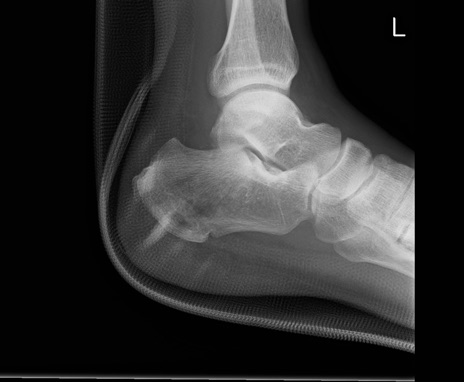

症例37 踵骨レントゲン(左側面像)

【症例】50歳代男性

【主訴】左踵部の痛み、腫脹

【現病歴】4日前に1.5m程度の高さのトラックの荷台から荷物と一緒に転落し、左足部を打撲。近医受診し、当院へ紹介受診となる。

【身体所見】左踵部の腫脹、圧痛あり。

異常所見と診断は?